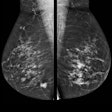

Leave no invasive breast cancer behind by using MRI